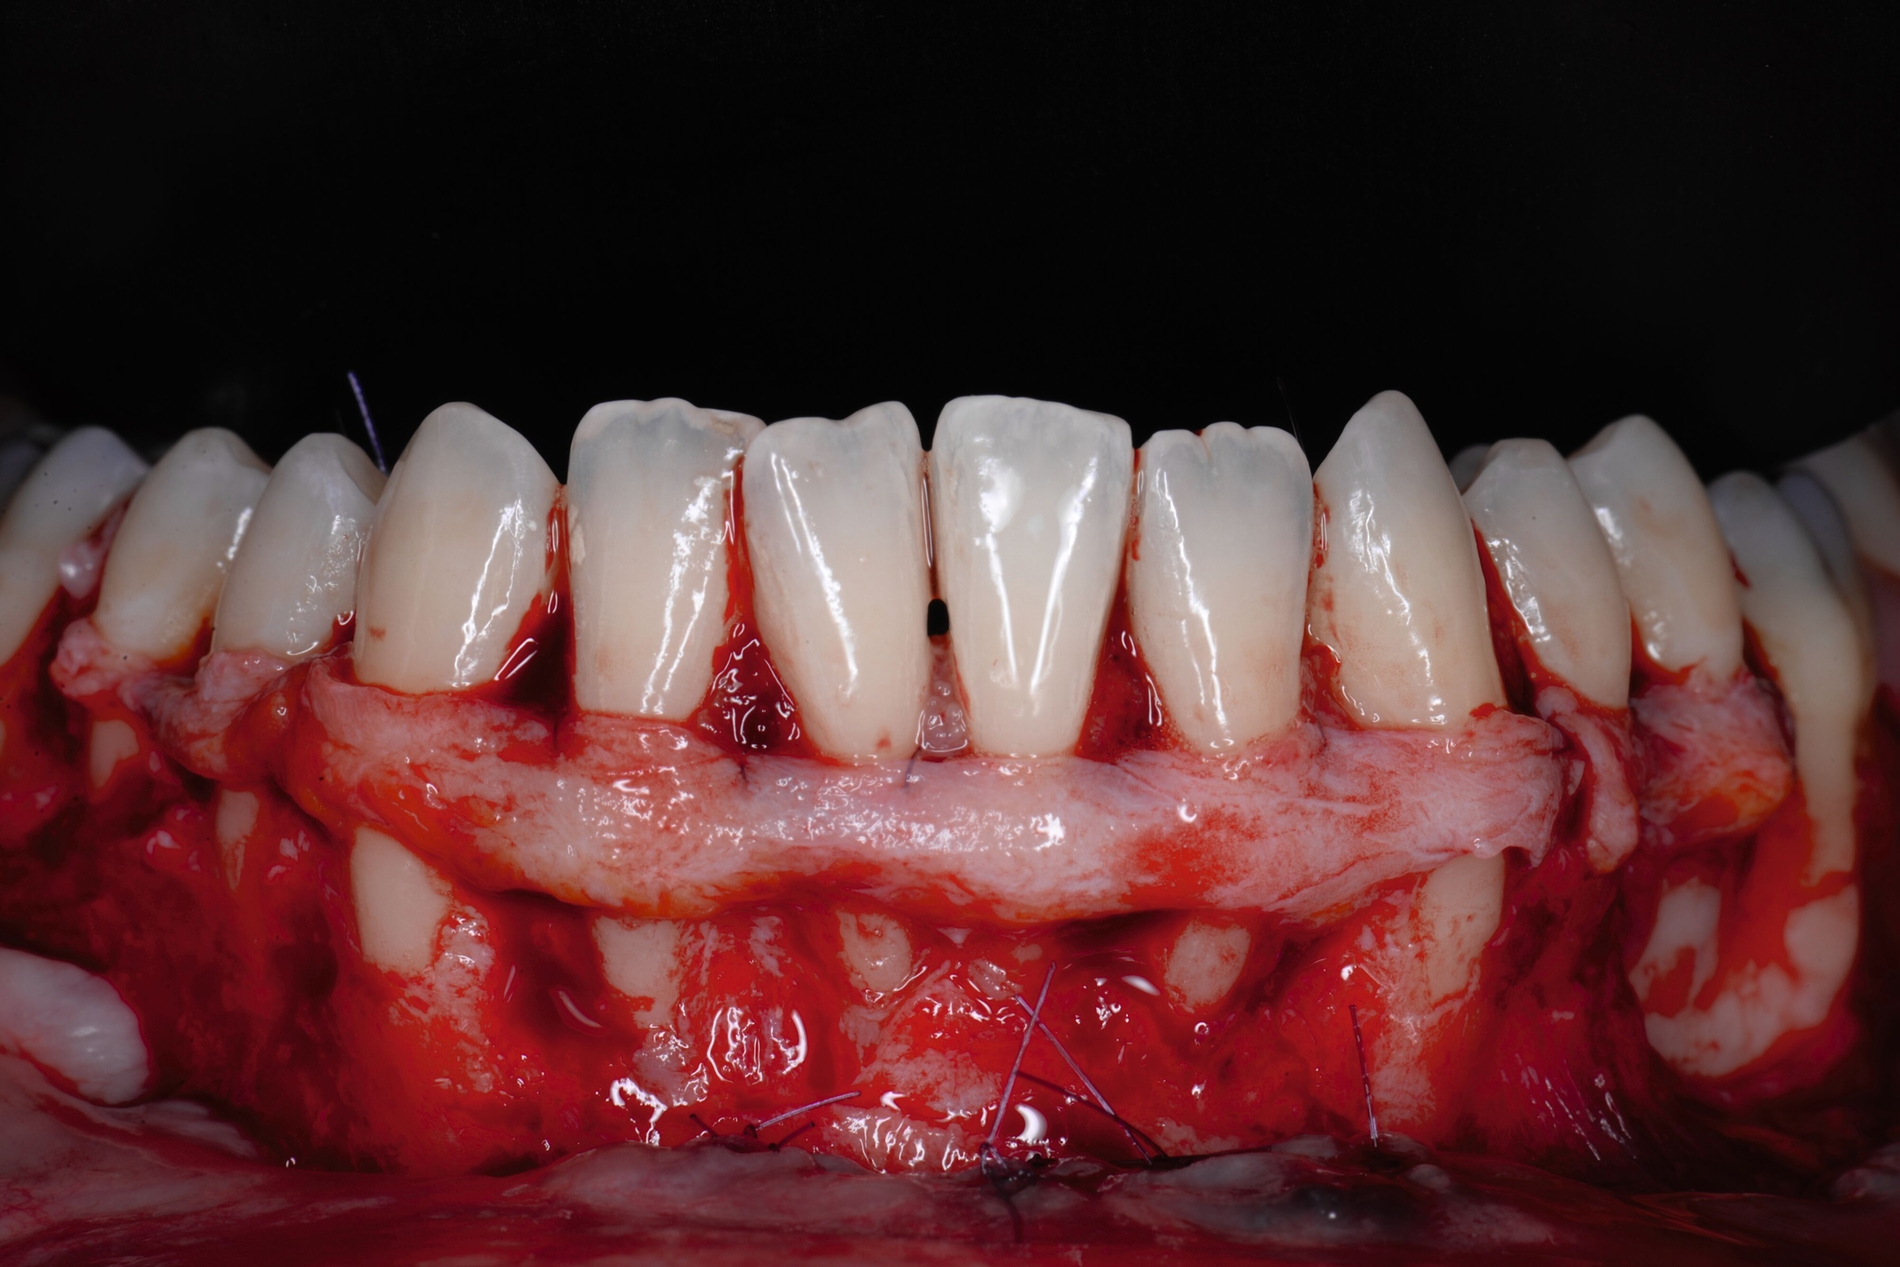

Tunkel et al. versuchten die Vorteile von Zucchellis Koronalem Verschiebelappen und Sculeans Lateral Geschlossenem Tunnel in einer Technik zu vereinen: dem Lateral Geschlossenen Koronalen Verschiebelappen (LCAF) [Tunkel et al., 2024] (Abbildung 3). Bei dieser Methode, mit der vor allem tiefe singuläre parodontale Rezessionen behandelt werden, wird die Koronalverschiebung ohne Entlastungsinzisionen kombiniert mit dem lateralen Verschluss der tiefen parodontalen Rezession.

Das Vorgehen ist hier wie folgt: Zunächst wird im Bereich der tiefen Rezession der Gingivarand geringfügig exzidiert, um ein Zusammenwachsen der geschlossenen Lappenanteile zu ermöglichen. Anschließend wird der Schnitt in horizontaler Richtung durch leicht bogenförmige Schnittführungen auf Höhe der Schmelz-Zement-Grenze erweitert, um mindestens zwei Zähne rechts und links von der Rezession (Abbildung 3b). Im Unterkiefer-Frontzahnbereich, wo die Rezessionen heutzutage am häufigsten vorkommen, sollte der Lappen mindestens von Eckzahn zu Eckzahn gebildet werden, um ein harmonisches Ergebnis nach Abheilung zu erreichen. Auf vertikale Entlastungsinzisionen kann komplett verzichtet werden. Anschließend erfolgt die Lappenpräparation nach dem bereits für koronale Verschiebelappen gängigen Prinzip teilschichtig-vollschichtig-teilschichtig.

Die Papillenbereiche werden mit dem Skalpell scharf vom Periost abgelöst. Dann wird das Periost durchtrennt und bis zur mukogingivalen Grenze ein vollschichtiger Lappen gebildet. Nach Überschreiten dieser wird wieder zweischichtig präpariert. Hierdurch wird eine gute Mobilisation des Lappens erreicht, die eine ausreichende Koronalverschiebung ermöglicht. Entgegen dem in früheren Jahren propagierten komplett teilschichtigen Vorgehen, kann durch dieses Verfahren die Gefahr von Lappenperforationen signifikant gesenkt werden, da diese insbesondere im Bereich der mukogingivalen Grenze auftreten. Nachdem die Lappenareale mesial und distal der Rezession gelöst sind, können diese durch zwei bis drei feine monofile Nähte miteinander verbunden werden (Abbildung 3c). Sobald durch diese Naht ein zusammenhängender koronaler Verschiebelappen entstanden ist, werden die Papillenbereiche koronal des gebildeten Lappens entepithelialisiert. Nach Entnahme eines Bindegewebstransplantats oder entepithelialisierten freien Schleimhauttransplantats wird die Wurzeloberfläche mit EDTA-Gel konditioniert und anschließend werden Schmelz-Matrix-Proteine aufgetragen (Abbildung 3d). Diese bewirken die Bildung eines new attachment und fördern zudem die Wundheilung, was gerade bei den delikaten lateralen Verschiebelappen von Vorteil sein sollte [McGuire und Cochran, 2003; Almqvist et al., 2011; Thoma et al., 2011; McGuire et al., 2016]. Anschließend wird das Transplantat durch Nähte ausgehend vom oralen Papillenbereich fixiert (Abbildung 3e). Zuletzt wird der Lappen mit sogenannten doppelten Umschlingungsnähten im Bereich der Papille durch Zug nach koronal und oral fixiert, was eine perfekte Positionierung ermöglicht [Zuhr et al., 2009] (Abbildung 3f). Hierbei muss darauf geachtet werden, dass der Lappen die Schmelz-Zement-Grenze um mindestens 2 mm überdeckt, um eine hundertprozentige Wurzeldeckung erwartbar zu machen [Pini Prato et al., 2005].

Der Lateral Geschlossene Koronal Verschobene Lappen ermöglicht eine annähernd narbenfreie Deckung singulärer parodontaler Rezessionen durch Verzicht auf vertikale Entlastungsinzisionen (Abbildung 3g). Das Lösen der Papillen im Rahmen der Verschiebung ermöglicht eine deutliche Anhebung des Lappens und somit durch großzügige Überdeckung das Erreichen vollständiger Wurzeldeckungen. Durch den lateralen Verschluss im Rahmen der tiefen, über die mukogingivale Grenze hinausgehenden Rezession kann keratinisierte Gingiva im Bereich dieser hergestellt und eine übermäßige Mobilisation und damit Einschränkung des Vestibulums verhindert werden.